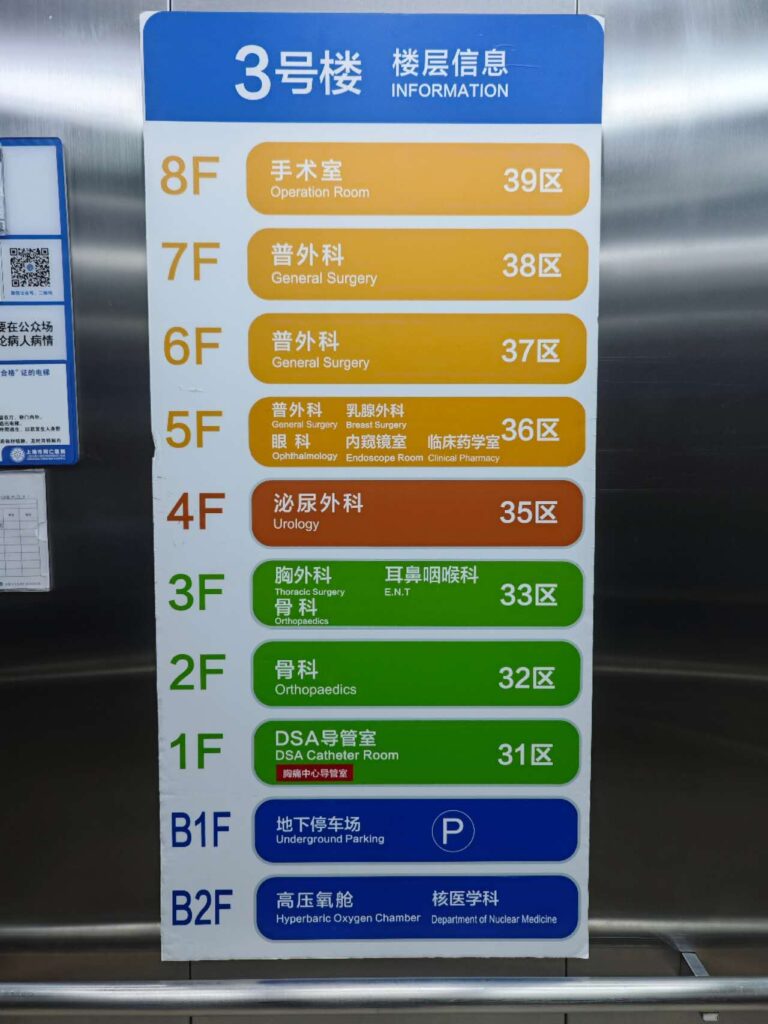

Four days after the injury, I finally went to the emergency room. An X-ray revealed a spiral fracture of the fifth metatarsal and the need for urgent surgery. I wasn’t allowed to go home; instead, I was admitted to a hospital room, where I waited for the operation two days later.

From 22nd to 26th of October 2024 at the Tongren Hospital (Shanghai Jiaotong University School of Medicine), Shanghai